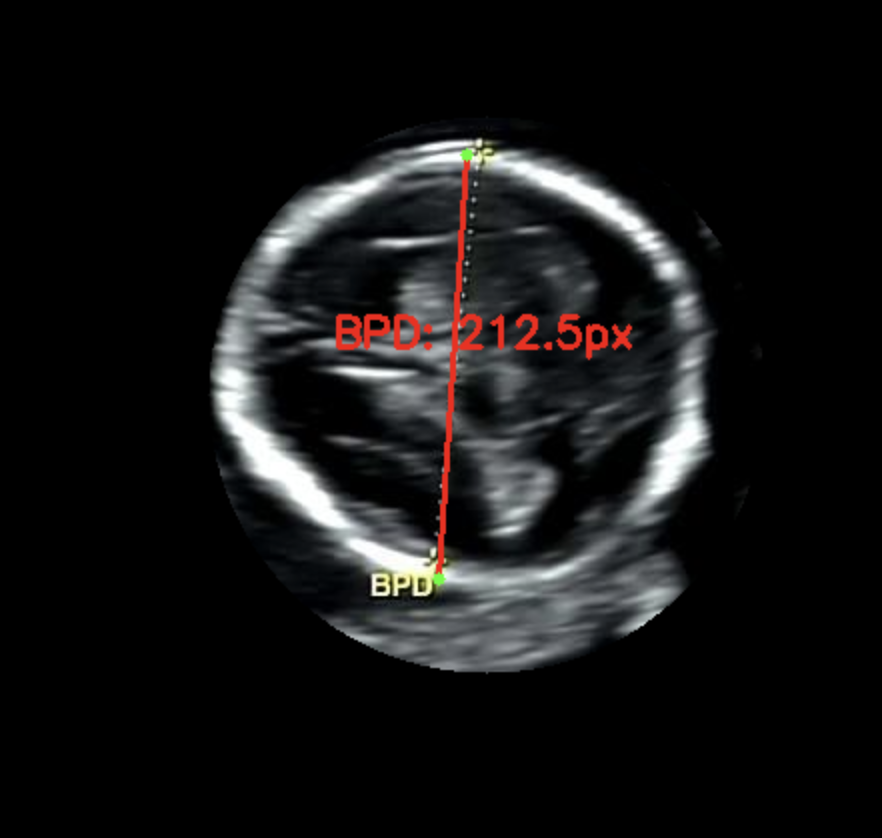

대부분의 녹화본에는 스케일바가 있다. 여기서 픽셀 당 실제거리 (cm/pixel) 을 구할 수 있다고 판단했다. 그래서 내가 원하는 두 점 사이의 거리 (단순 픽셀 거리) 곱하기 cm/pixel 을 곱하면 실제 거리를 구할 수 있다고 생각했다. cm/pixel 이 배율인 셈이다.

실제로는 8.22 cm 로 기록되었고 내가 측정한 기록값은 8.29 cm 로 오차는 크지 않았다. 가설을 검증했고 충분히 해볼 만하고 생각했다. 다만 아래와 같은 해결 과제가 남았다. 첫 번째는 계산 시 (14 cm / 스케일 바 픽셀 거리) 로 하드코딩해서 배율을 계산했기 때문에 스케일 바를 검출하는 이미지 전처리 과정이 필요했다. 두 번째는 초록색 영역 검출 시 곡선과 같은 형태 두 개를 찾고 그 사이 거리를 찾는 식이라 이미지별로 다소 편차가 있었다. 내 눈에는 원처럼 보이는데 컴퓨터가 인식할 때는 원으로 인식하지 않아서 반원 곡선 형태를 찾도록 코딩했다.

이미지 전처리 과정을 거쳐서 원하는 영역을 추출하도록 개선했다. 이미지 전 처리 과정이 잘 구축해두면 정확도가 높아진다. 이미지 전 처리 과정은 다음과 같다: